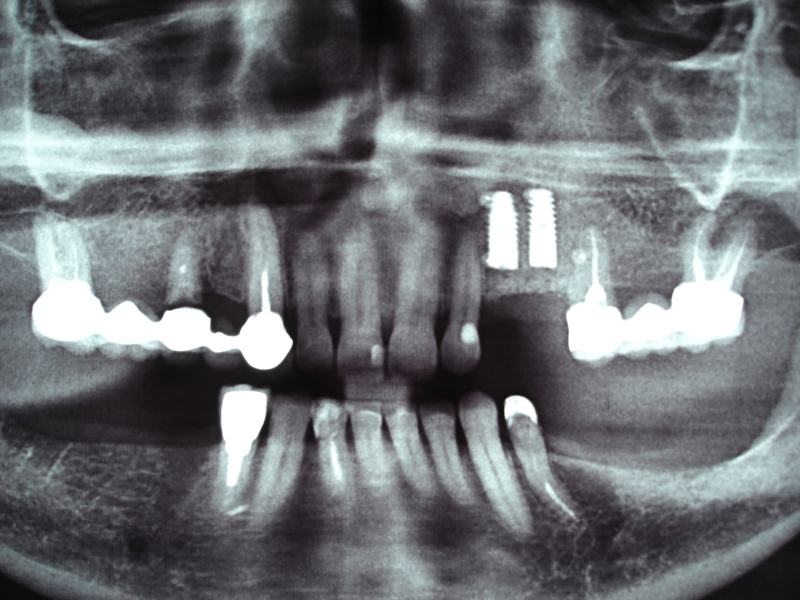

Initial x-ray showing bone loss around implants placed 5 years ago in another dental clinic